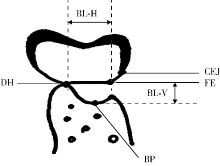

Effect of concentrated growth factors in guided tissue regeneration for the treatment of mandibular molar furcation lesions

| [14] | Fei LI,Jing QIAO,Jin-yu DUAN,Yong ZHANG,Xiu-jing WANG. Effect of concentrated growth factors combined with guided tissue regeneration in treatment of classⅡ furcation involvements of mandibular molars [J]. Journal of Peking University (Health Sciences), 2020, 52(2): 346-352. |